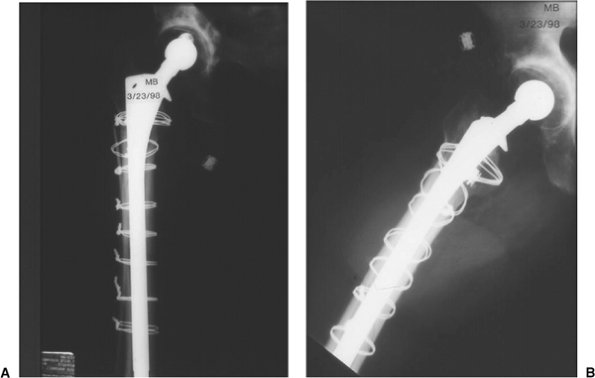

![]() |

|

Figure 45.4. AP (A) and lateral (B) radiographs of final revision construct with long-stem implant, struts, and multiple Luque wires.